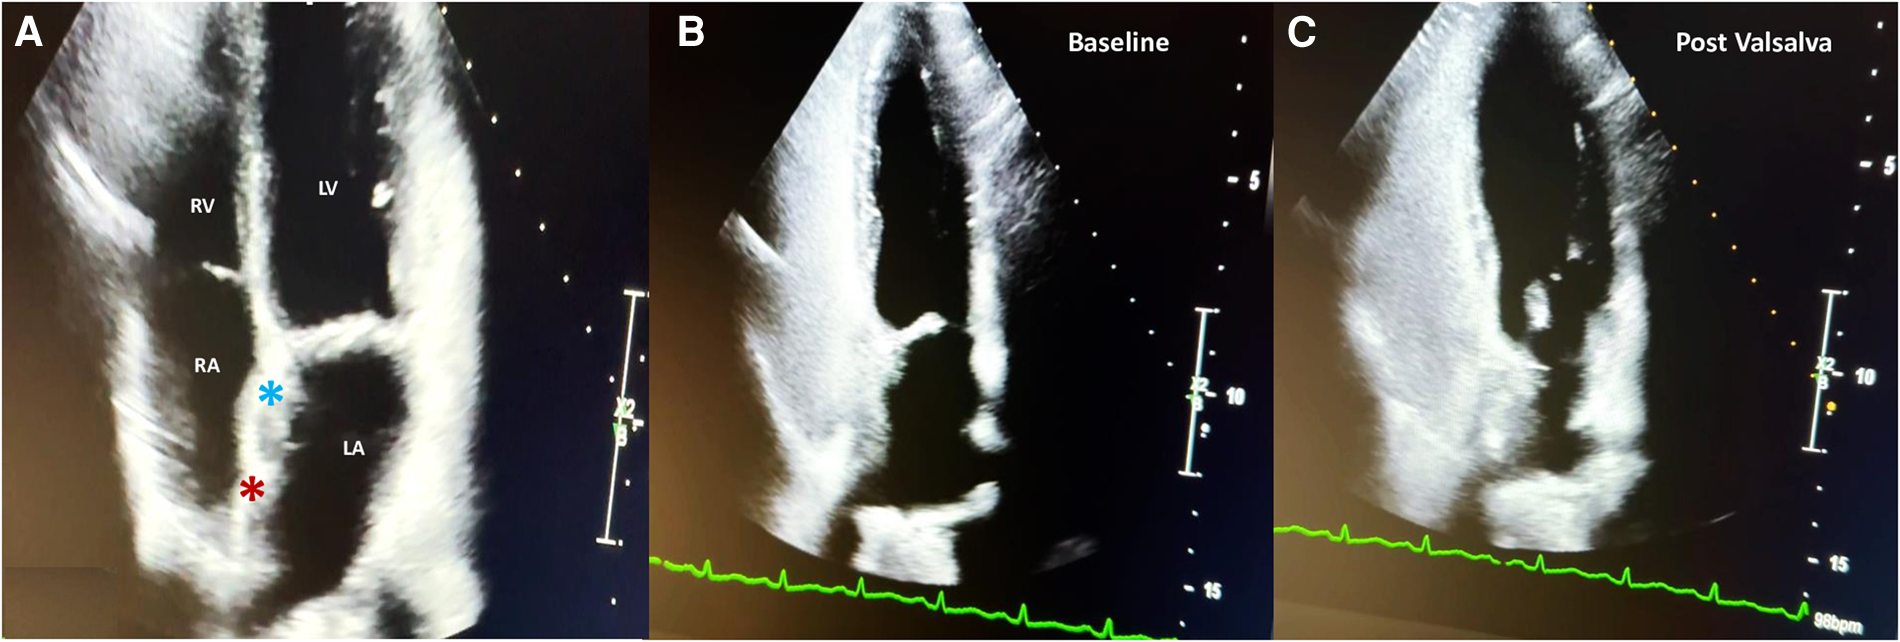

Figure 4

Two-year follow-up 2D TTE color Doppler in the apical four-chamber view showing the correct interaction between the UNI 33/33-mm device (light blue asterisk) and the Figulla Flex II 16/18-mm device (red asterisk) (A); contrast 2D TTE confirming abolition of the residual shunt at baseline (B) and after the Valsalva maneuver (C).